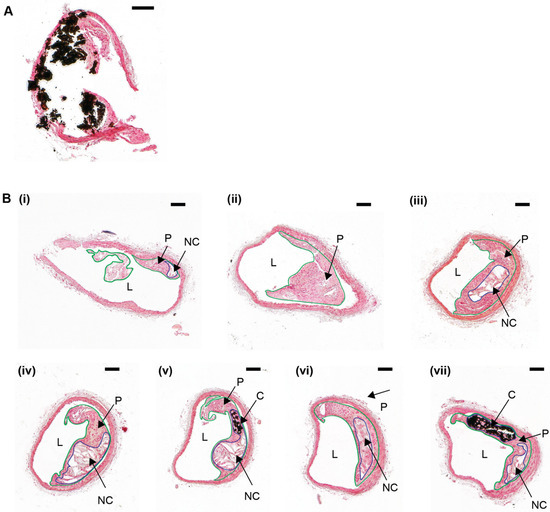

Figure 2.

Atherosclerotic plaque calcification heterogeneity in a serially-sectioned brachiocephalic artery from an ApoE−/− mouse. (A) Formalin-fixed brachiocephalic artery tissue section from a 10-week old ApoE−/− mouse fed a high fat, high cholesterol diet for 28 weeks. The tissue was taken through a series of graded alcohols and rehydrated, stained with von Kossa, and then counterstained with nuclear fast red. A large calcification (stained black) has “dropped out” during sectioning, resulting in shearing artefacts and tissue damage. (B) A formalin-fixed brachiocephalic artery from a 10-week old ApoE−/− mouse fed a high fat, high cholesterol diet for 28 weeks was serially sectioned, collecting a total of 120 sections, with each section—10 µm in size. Tissue sections were collected from the brachiocephalic artery bifurcation (B)/(i) into the main brachiocephalic artery trunk (B)/(ii–vii), and sections every 200 µm intervals were stained with von Kossa and counterstained with nuclear fast red. The atherosclerotic plaque is outlined in green. The necrotic core, which is an internal lipid-rich region lacking in collagen or cell nuclei but contains cell debris, is outlined in blue. Both atherosclerotic plaque and calcification heterogeneity are noted throughout the brachiocephalic artery. Lumen (‘L’); Plaque (‘P’); Necrotic core (‘NC’); Calcification (‘C’). Scale bar = 100 µm.

Several studies have also identified a marked variation in calcium deposition over relatively short lengths of a blood vessel [73,74]. This issue is amplified in calcified atherosclerotic lesions, in which diffuse microcalcifications and focal macrocalcifications can be identified within the same lesion (Figure 2(B)/(i–vii)) [75,76]. Therefore, it is necessary (but not always implemented) for multiple serial tissue sections to be cut, stained, imaged, and analyzed from a single blood vessel—this is laborious and time-consuming. As a result, experimental bias and error can occur by selecting areas of analysis either randomly along the profile of the vessel, or at the site of maximum calcification. Thus, key features such as micro-calcifications and extracellular matrix remodeling (e.g., elastin degradation [28,77,78]) may not always be detected.